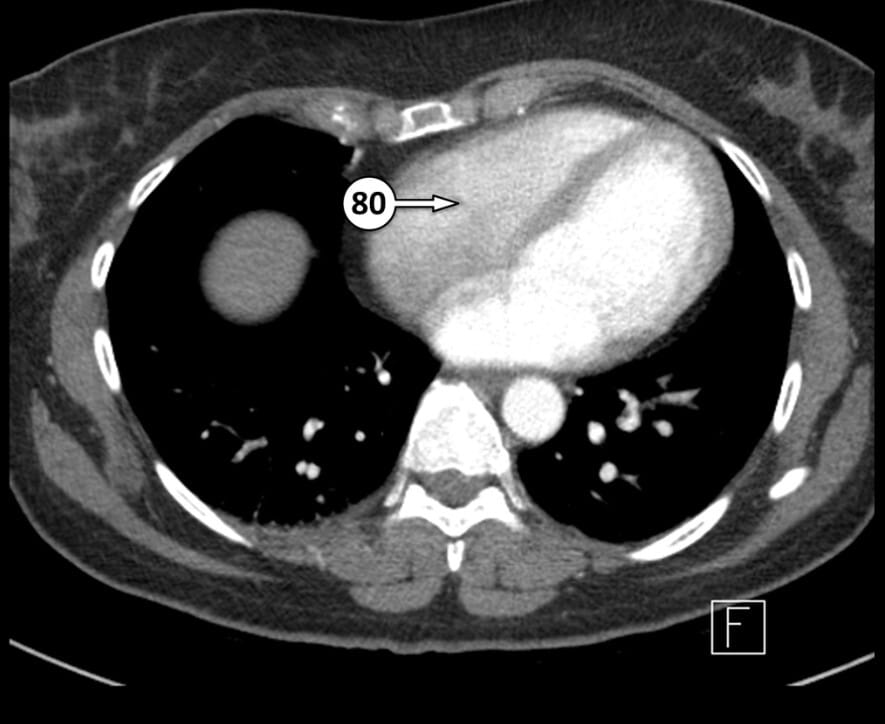

80. tricuspid valve (approximate location)